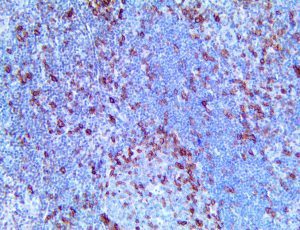

It is the ICU physician who is most likely to witness one of the deadliest manifestations of the abnormal immunological response, the cytokine storm syndrome (CSS). This response is also referred to by some as the cytokine release syndrome (CRS). CSS is characterized by continuous activation and expansion of macrophage and lymphocyte populations, which secrete large amounts of cytokines, causing the cytokine storm. This massive cytokine release is akin to hemophagocytic lymphohistiocytosis (HLH) disease, a syndrome characterized by initial unchecked and persistent activation of cytotoxic T lymphocytes and NK cells.

Clinical and laboratory manifestations of HLH include fever, enlarged liver and/or spleen, neurologic dysfunction, coagulopathy, liver dysfunction, cytopenias (i.e., low levels of erythrocytes, leukocytes, and/or platelets), hypertriglyceridemia, hyperferritinemia, hemophagocytosis, and eventually diminished NK cell activity as the immune system becomes progressively paralyzed. HLH can be familial (primary HLH) or secondary to another disease process (sHLH), such as rheumatic disease, in which it is referred to as macrophage activation syndrome (MAS, characterized by elevated ferritin).